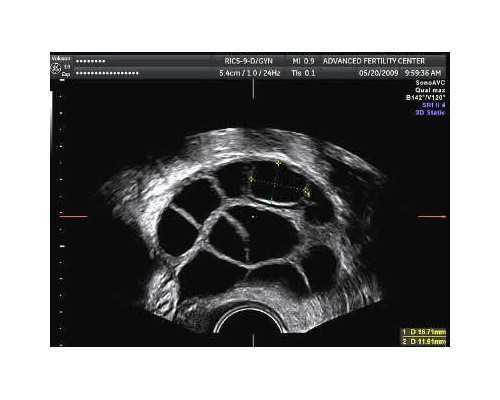

1. 术前检查费用:供卵自怀助孕之前,夫妻双方都是需要积极配合医生进行一次较为全面的身体检查的,其检查费用就在5000元左右;2. 胚胎培养和移植试管婴儿费用:术前检查完成之后,医生就会利用供卵卵子与男性取出来的精子进行结合使其发生受精和培养,并在适宜的时间进行胚胎移植,其费用就在7000元左右;3. 移植后保胎及验孕费用:供卵自怀移植胚胎后都是需要进行保胎的,同时在移植试管婴儿后的半个月需去医院抽血查hcg,以确定怀孕与否,其费用在2000元左右;4. 单个精子注射费用:供卵自怀患者若是选择的二代试管,在男性取精后医生会将单个精子进行注射,以提高精卵受精成功率,该项技术的费用在5000-8000元左右;5. 胚胎检测费用:若是供卵自怀患者选择三代试管技术进行助孕,在移植胚胎之前,实验室人员就会进行胚胎检测,以确定胚胎是否存在染色体异常等问题,以排除有质量问题的胚胎,其费用在30000-50000元左右。广州目前做供卵试管婴儿比较好的医院有好几家,省内知名度比较高的医院如广州医科大学附属第三医院、广东省人民医院、中武警广东省总队医院等,这里分享几家网友亲身经历,并推荐的比较热门的医院,包括生殖中心简介、费用与成功率的简单介绍: